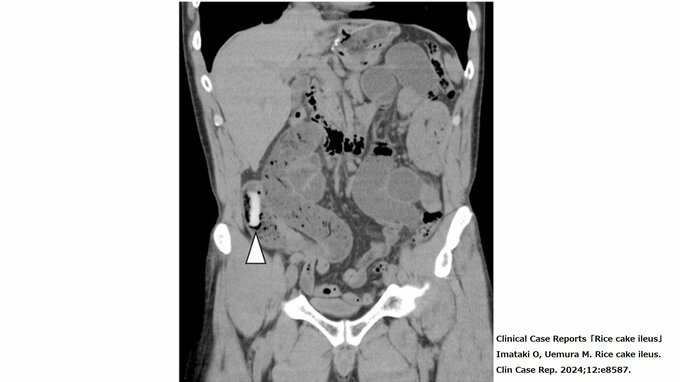

餅による腸閉塞は窒息事故ほどの発生件数はないが、毎年数人はいるようで学術論文での言及もいくつかある。香川大学・今滝修さんの論文「Rice cake ileus」には、実際に餅が腸に詰まっているCT画像も掲載されている。

CT画像には、白い4cm程度の細長い形状のものが写っている。これが体内で硬くなった餅で、腸の流れが悪くなって「餅による腸閉塞」になるのだという。

ここまではっきりと画像で餅が詰まっているのがわかるとは、驚きである。